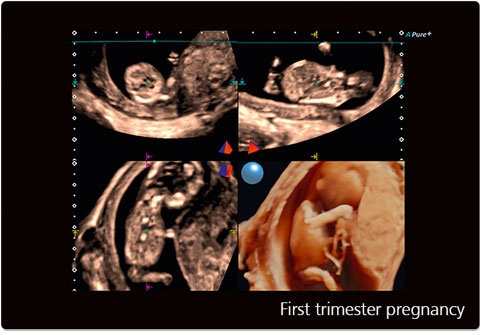

• MPR - функция мультипланарной реконструкции для визуализации исследуемой области в 3-х ортогональных плоскостях

• Программа анализа сердца плода в трех проекциях в реальном времени 4D Stick;

• STIC - исследование сердца плода в режиме объёмной визуализации